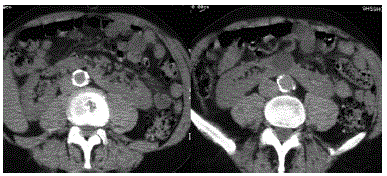

Paciente adulto, jovem, com trauma abdominal e hematúria, realizou exame de TC sem contraste.

Correlacionando com a imagem disponibilizada, marque a relação verdadeira.